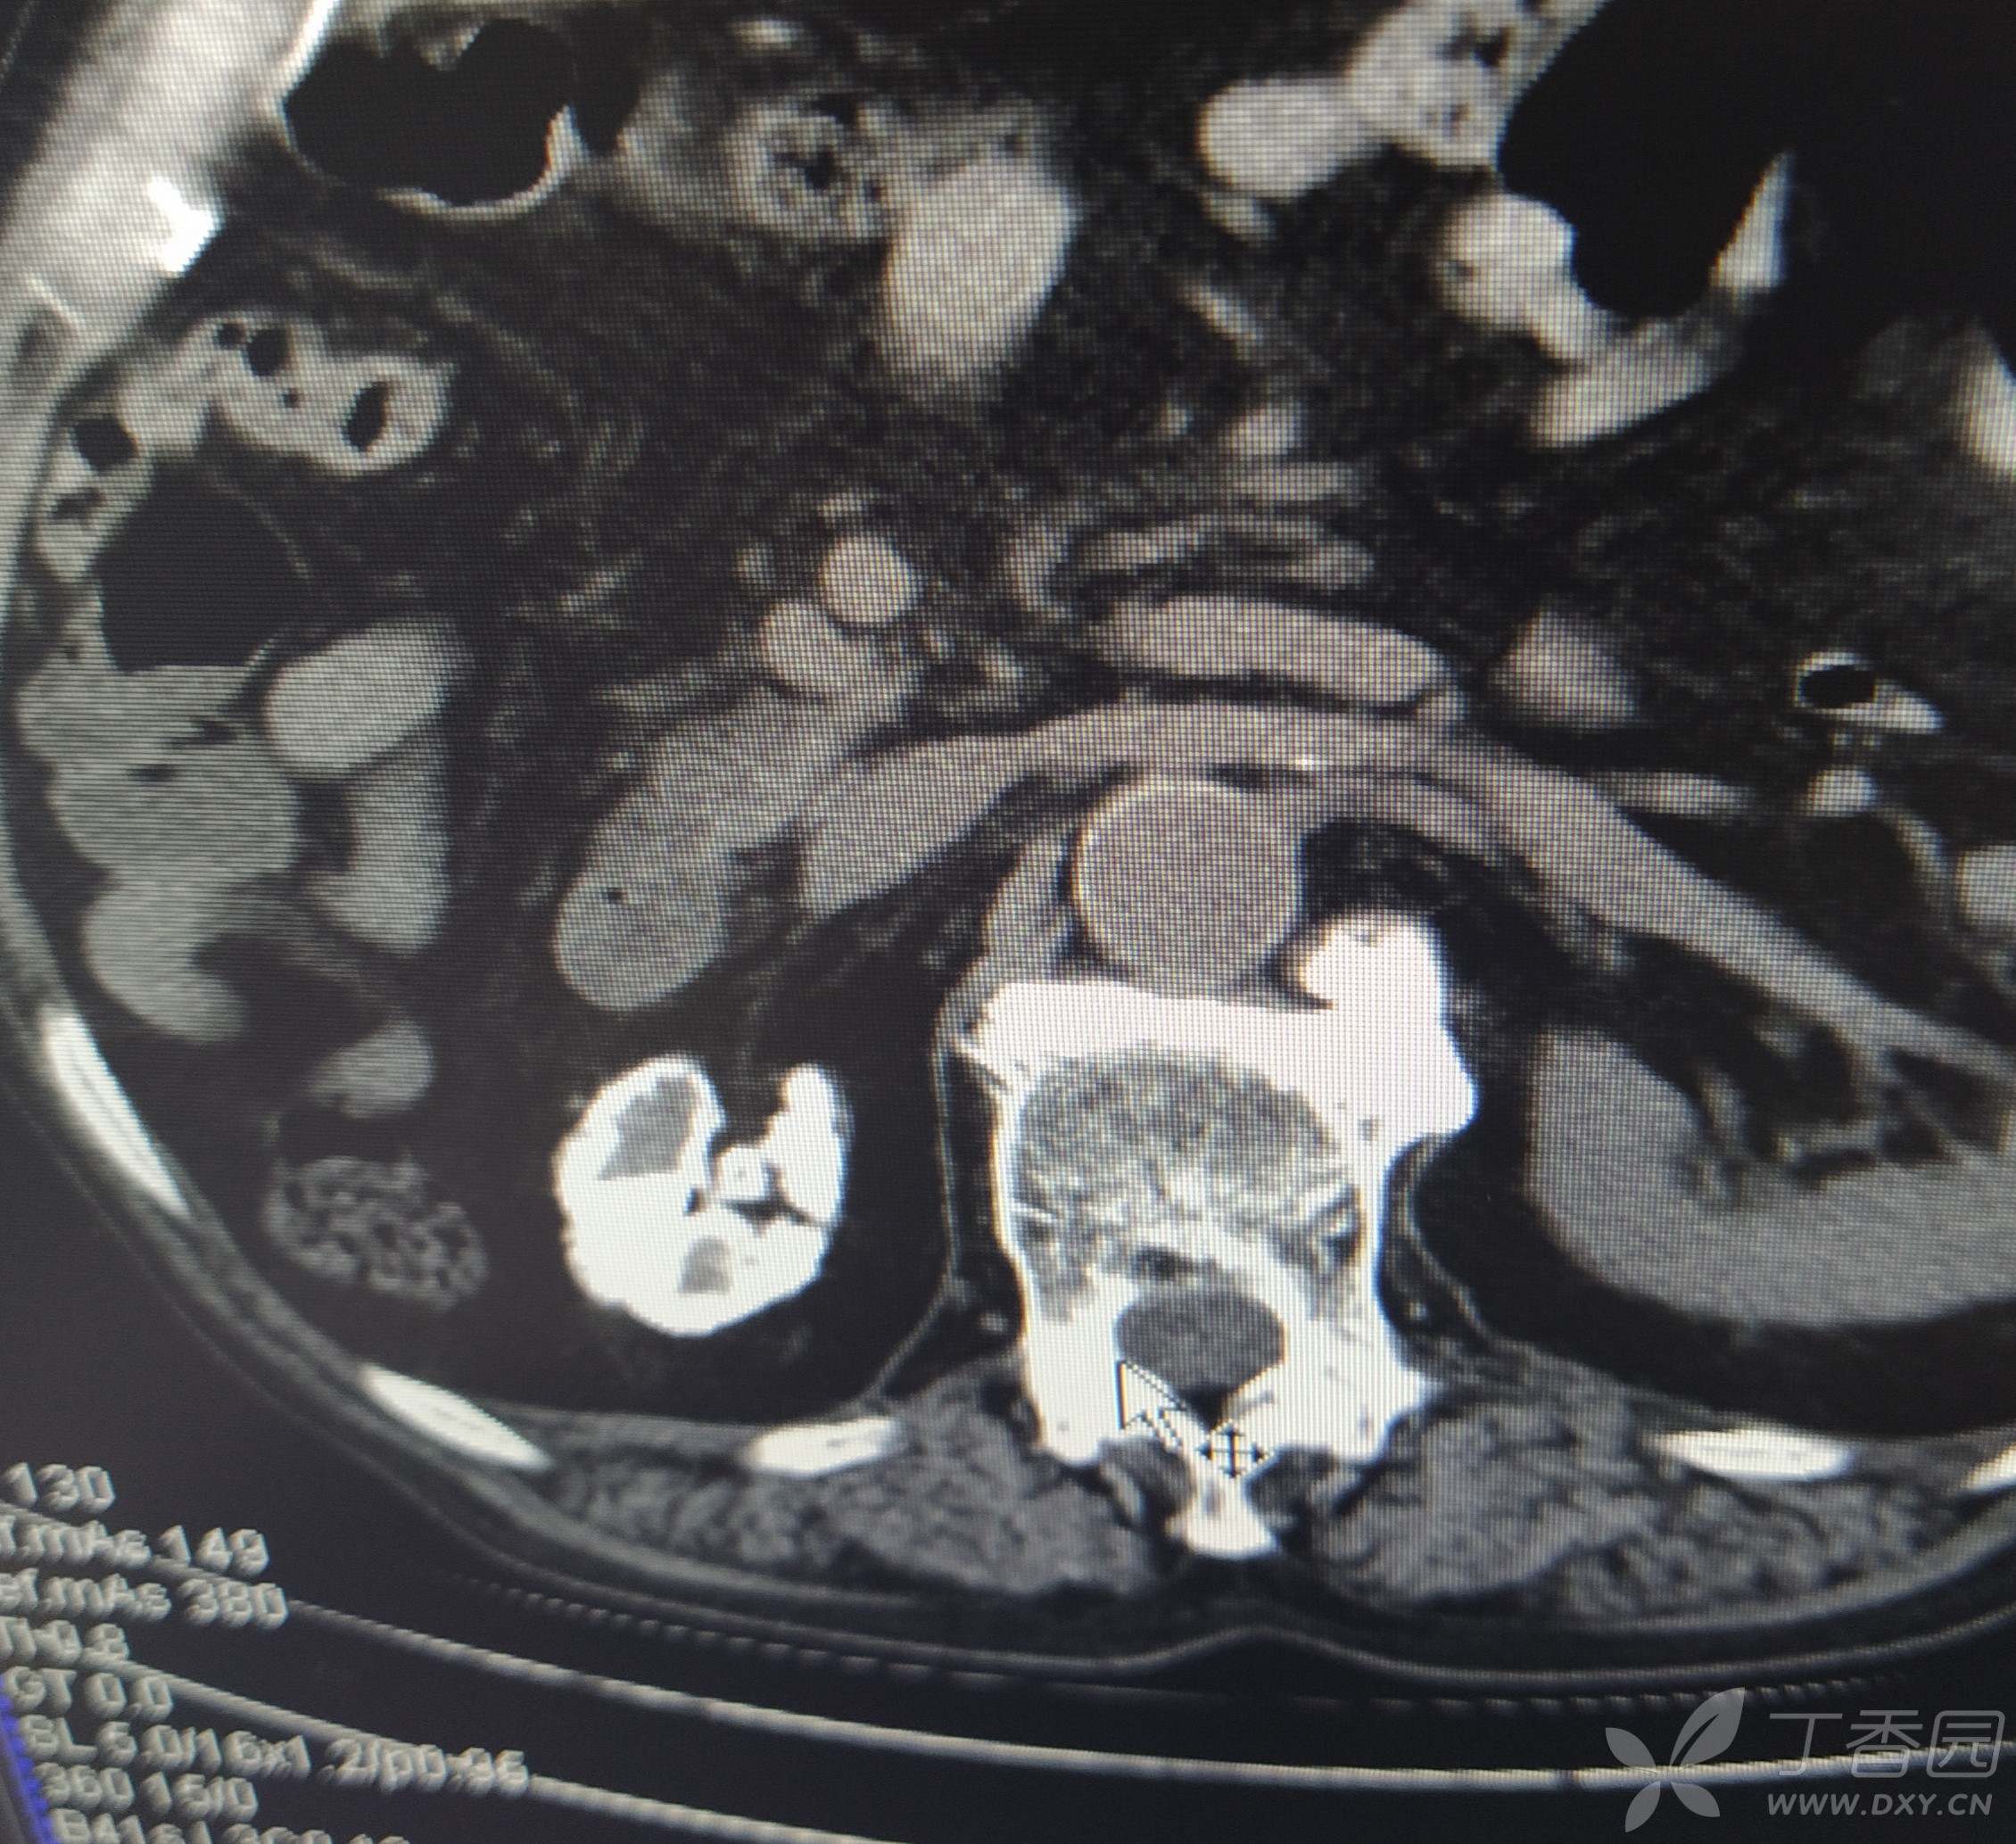

男,80岁,体检发现右肾呈坏死性钙化,肾周边钙化伴声衰减,CT可见明显钙化